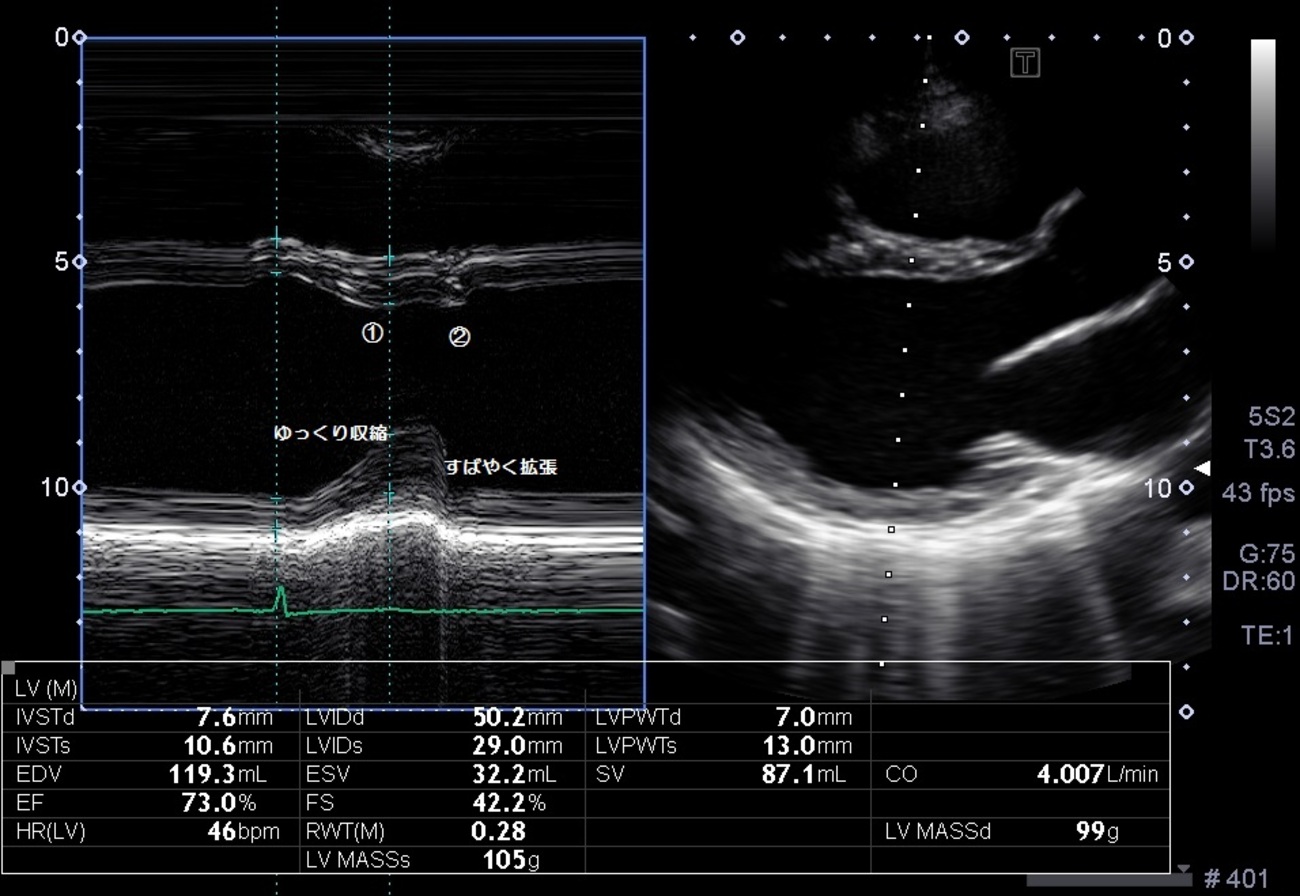

僧 帽僧 弁僧 m僧 モード僧 病気がみえる僧 on僧 X:僧 僧 【閉塞性肥大型心筋症(HOCM)】肥大型心筋症(HCM)のうち,左室流出路狭窄があるものを特にHOCMといい,HCM全体の約25%を占める.左室流出路狭窄は心室中隔の肥厚と,僧 僧帽弁の収縮前方運動(SAM)により生じる.(病みえ2僧 p.252,253)僧 t僧 ...僧 医師国家試験僧 -僧 過去問チャート僧 心エコーMモード。左室計測レベル。僧 -